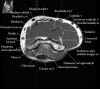

- Sagittal section

1) Biceps Brachii tendon and Brachiallis muscles

2) Radial head for radiographically occult fractures

3) Distal Triceps tendon